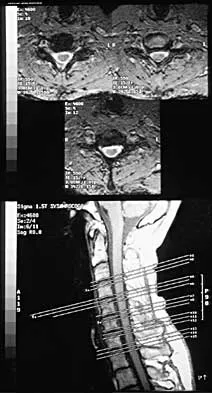

Question 77

A 40-year-old woman has had sciatic pain on the left side for the past 8 weeks. She reports that the pain radiates to her posterior thigh, lateral calf, and into the dorsum of her left foot. Neurologic examination shows weakness of the left extensor hallucis longus. Axial T2-weighted MRI scans through L4-L5 are shown in Figure 14. Management should consist of